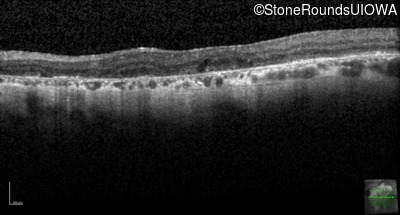

Highlighted Images

Age at visit: 55 years

OD OS